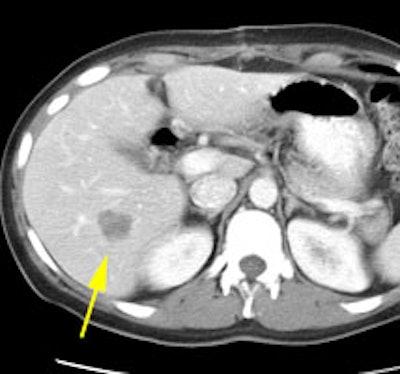

Initial staging for extrahepatic metastases: The patient below underwent FDG PET imaging to assess for extrahepatic metastatic disease prior to definitive surgical intervention. The PET exam demonstrates uptake within two hepatic metastases (black arrows on PET scan and yellow arrows on CT images) and in the patients primary colon cancer (blue arrow on PET scan and white arrow on CT image). No other sites of abnormal tracer uptake were identified which supports surgical intervention in this case. |